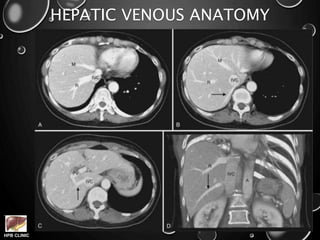

HEPATIC VENOUS ANATOMY